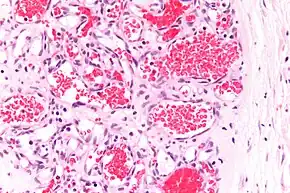

A precise history of the growth characteristics of the IH can be very helpful in making the diagnosis. In the first 4 to 8 weeks of life, IHs grow rapidly with primarily volumetric rather than radial growth. This is usually followed by a period of slower growth that can last 6–9 months, with 80% of the growth completed by 3 months. Finally, IHs involute over a period of years.[36] The exceptions to these growth characteristics include minimally proliferative His, which do not substantially proliferate[35] and large, deep IHs in which noticeable growth starts later and lasts longer.[36] If the diagnosis is not clear based on physical examination and growth history (most often in deep hemangiomas with little cutaneous involvement), then either imaging or histopathology can help confirm the diagnosis.[33][37] On Doppler ultrasound, an IH in the proliferative phase appears as a high-flow, soft-tissue mass usually without direct arteriovenous shunting. On MRI, IHs show a well-circumscribed lesion with intermediate and increased signal intensity on T1- and T2-weighted sequences, respectively, and strong enhancement after gadolinium injections, with fast-flow vessels.[33] Tissue for diagnosis can be obtained via fine-needle aspiration, skin biopsy, or excisional biopsy.[38] Under the microscope, IHs are unencapsulated aggregates of closely packed, thin-walled capillaries, usually with endothelial lining. Blood-filled vessels are separated by scant connective tissue. Their lumina may be thrombosed and organized. Hemosiderin pigment deposition due to vessel rupture may be observed.[39] The GLUT-1 histochemical marker can be helpful in distinguishing IHs from other items on the differential diagnosis, such as vascular malformations.[34]